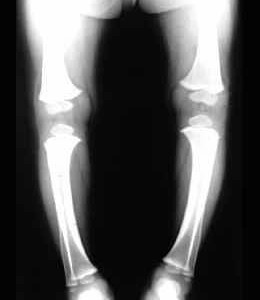

Göğüs kafesinde ve omurgada şekil bozuklukları görülür.Bu çocukların oturma ve yürümeleri gecikir.Yürüdükleri zaman ”O Bacak” veya ”X Bacak” denilen eğilmeler olur.Terleme ileri derecede artmış olu başın arka kısmındaki saçlarda seyrekleşme dikkati çeker.Vücudun enfeksiyonlara karşı direnci de düşük olduğu için üst solunum yolu hastalıkları ve zatürre sık görülür.Süt çocuklarında kandaki kalsiyum düşüklüğü,bazen bebeğin havale geçirmesine neden olabilir.